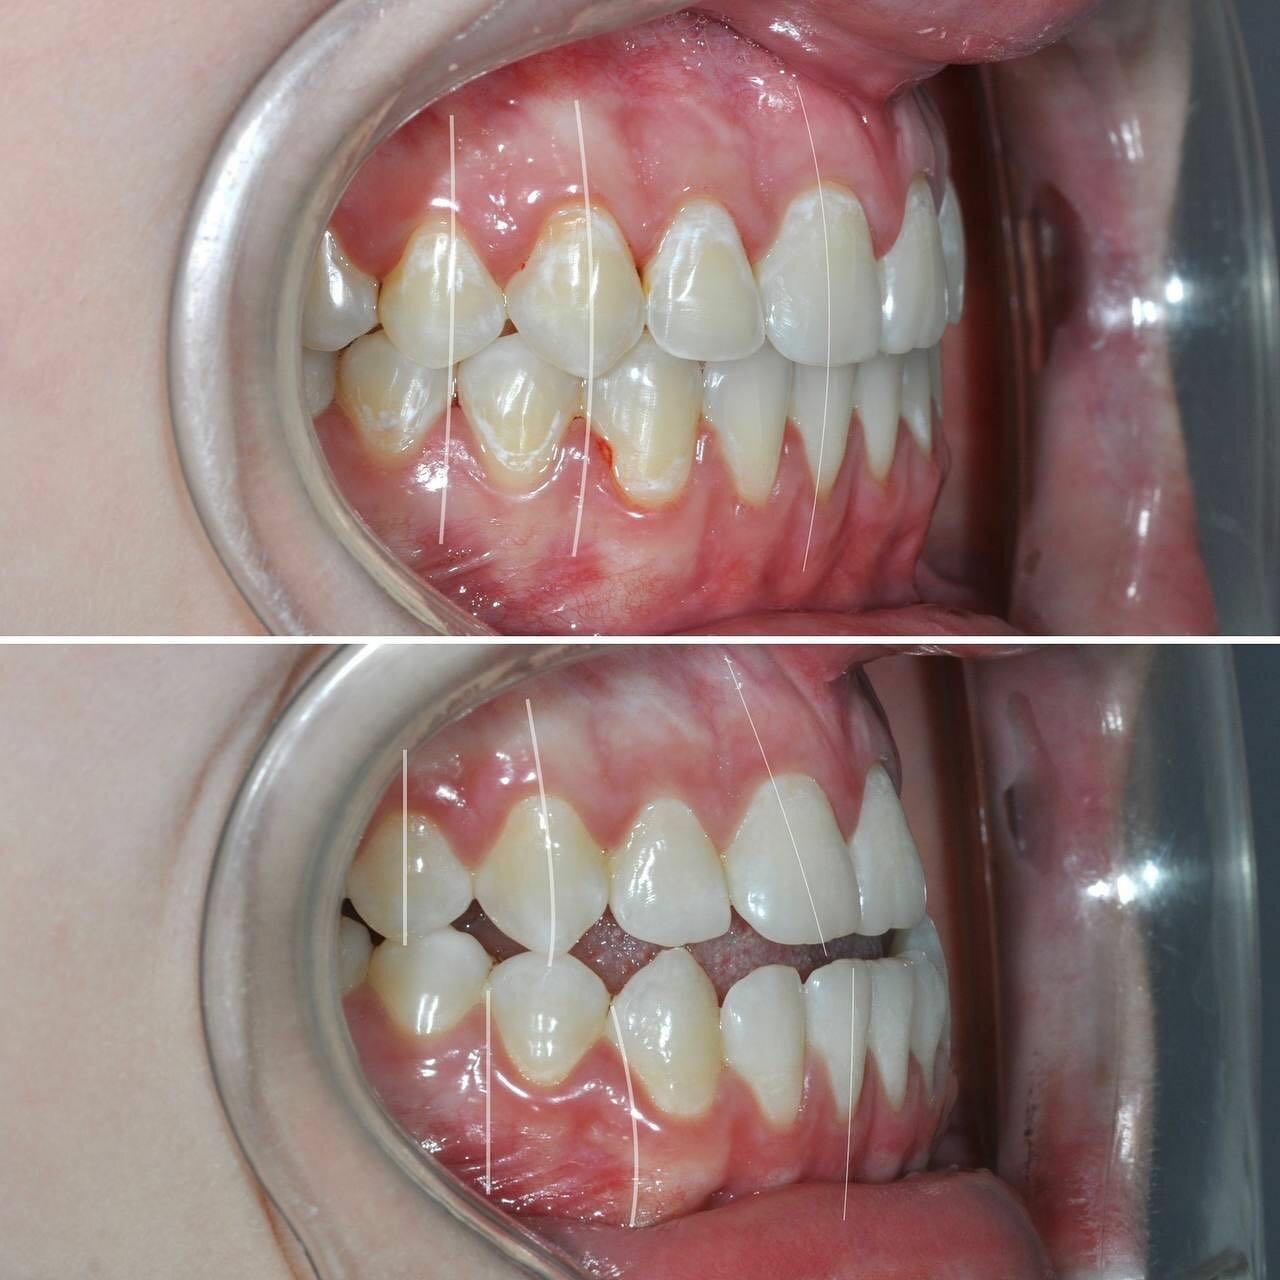

Клиника предоставляет услуги по всем основным направлениям стоматологии, включая общую стоматологию, ортодонтию, хирургическую и эстетическую стоматологию, а также детскую стоматологию. Среди дополнительных услуг: лечение кариеса, пломбирование, удаление зубов, имплантация, протезирование, отбеливание, установка виниров и брекетов, лечение десен и каналов, рентгенография, челюстно-лицевая хирургия и френулопластика.

- ортодонтия

- брекеты

- Положительные впечатления от консультации и установки брекетов.

Записывался на консультацию и дальнейшую установку брекетов для исправления прикуса. Впечатления на данный момент только положительные. Работа аккуратная, отношение вежливое, дополнительных услуг не навязывали.